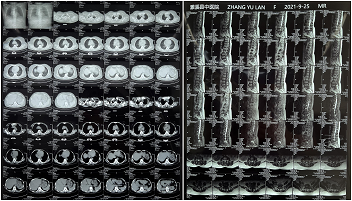

Preoperative MRI images of the patient

Intraoperative generation of cross-sectional, sagittal and coronal tomographic images and 3D stereoscopic images